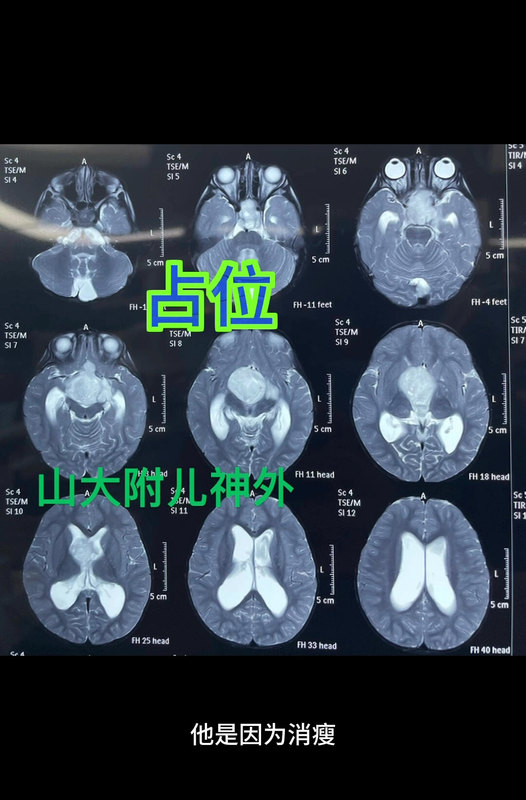

脑膜瘤和胶质瘤与肥胖有关吗? 减肥就是抗肿瘤

林松主任医师 北京天坛医院 神经外科

192人已读